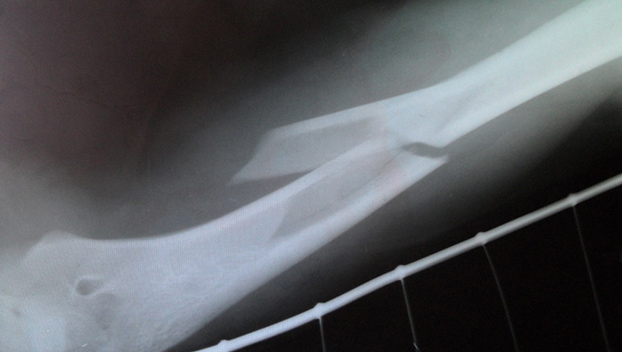

ЗображенняВосьмилетнего Владимира в травматологию привезли родители. Рентген показал перелом правой руки. Близкие и сам ребенок не стали скрывать от врачей правду. Выяснилось, что днем в школе Вова подрался с другим учеником, на четыре года старше. Да и раньше дети нередко конфликтовали друг с другом. На сей раз кулацкий бой между мальчиками завершился для младшего его участника печально.

Кроме перелома руки у ребенка диагностировали гематомы, множество царапин и ссадин. О происшествии травматологи сообщили в полицию. Там классифицировали случившееся как «нанесение телесных повреждений средней тяжести». Но поскольку наказание несовершеннолетнего законом не предусмотрено, решили строго взяться за родителей задиристого школьника. Кроме того, что семью как неблагополучную возьмут на учет, родителей еще привлекут к ответственности за плохое воспитание сына.